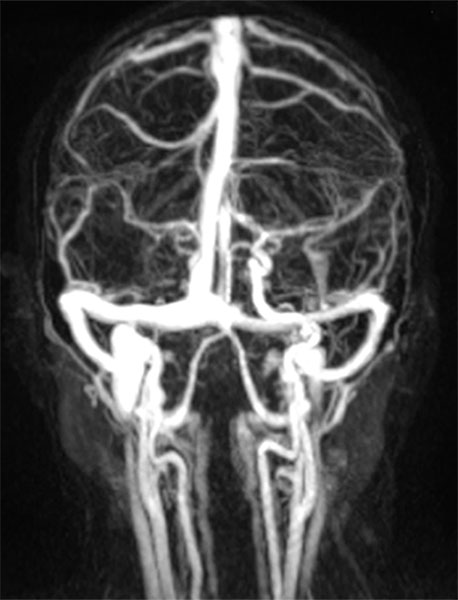

Coronal, contrast-enhanced, dynamic MR angiography, MIP imaging 33 s after injection of the contrast medium. The contrast dynamic is in the venous phase, the venous blood vessels are fully contrasted. The venous malformation itself does not accumulate any contrast medium at this time.

Coronal, contrast-enhanced, dynamic MR angiography, MIP displayed 124 s after injection of the contrast agent, thus a late venous phase. Only now does the venous malformation slowly accumulate some of the contrast medium (“pooling”).

Coronal, T1-weighted fat-suppressed MRI of the face after administration of contrast medium. The venous malformation enriches the contrast medium more clearly after 4 minutes, but relatively slowly and not yet completely at the time of imaging.